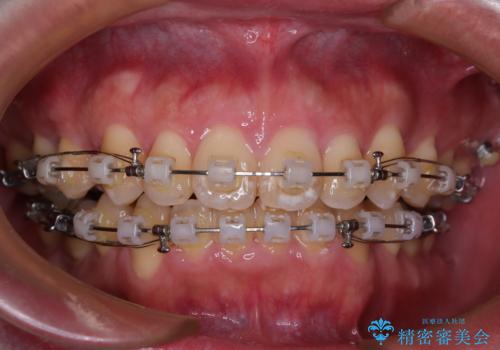

- クリアブラケット

2年から2年半の治療期間を想定しており、予定通りの期間で無事に終了することができました。

唇や顎先に力を入れないなくてもスムーズに唇を閉じることができるようになりました。